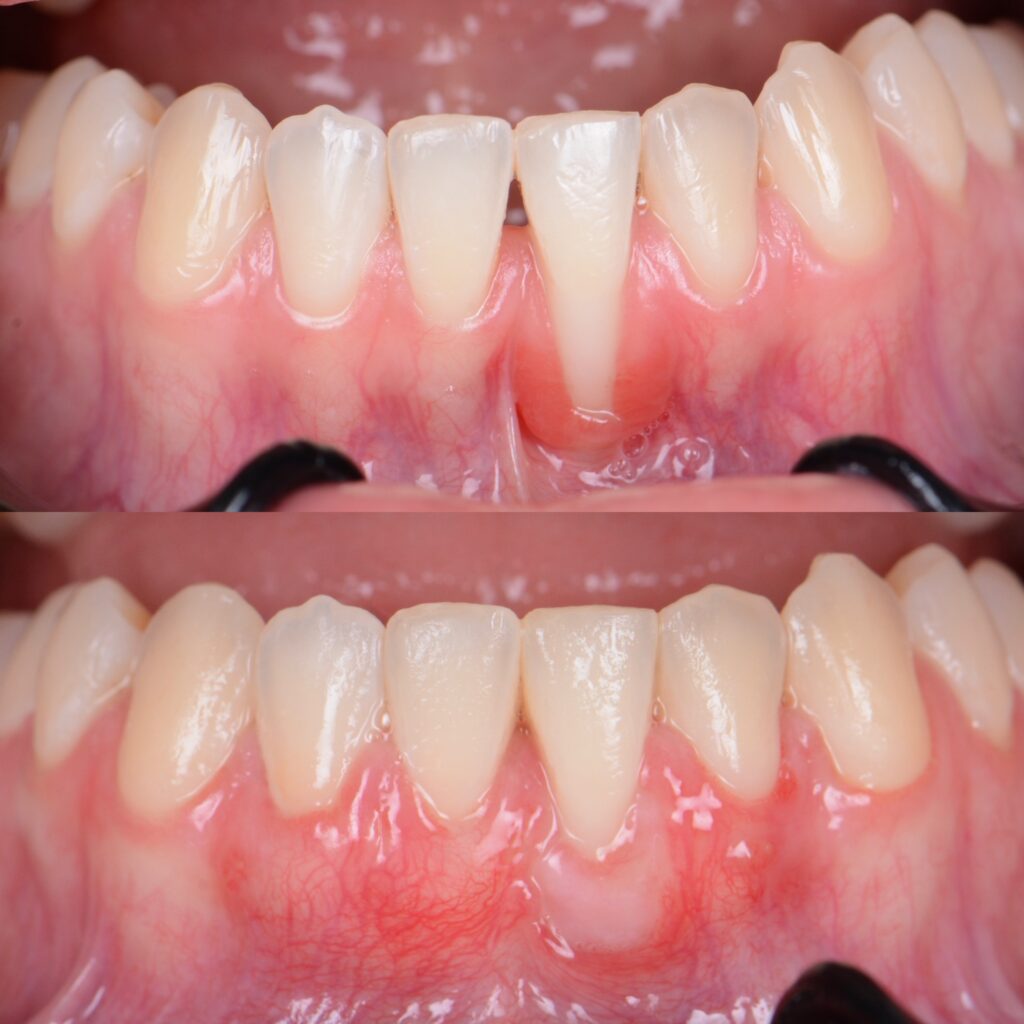

Sie finden einige Vorher/Nachher Fotos sowie Behandlungsbeispiele von Patienten die Dr. Azzawis Praxis wegen Zahnfleischrückgang aufgesucht haben.

Klinische Fälle

Case 14

Vollkommene Harmonie – Veneers und ästhetische Zahnfleischkorrektur für ein beeindruckendes Lächeln